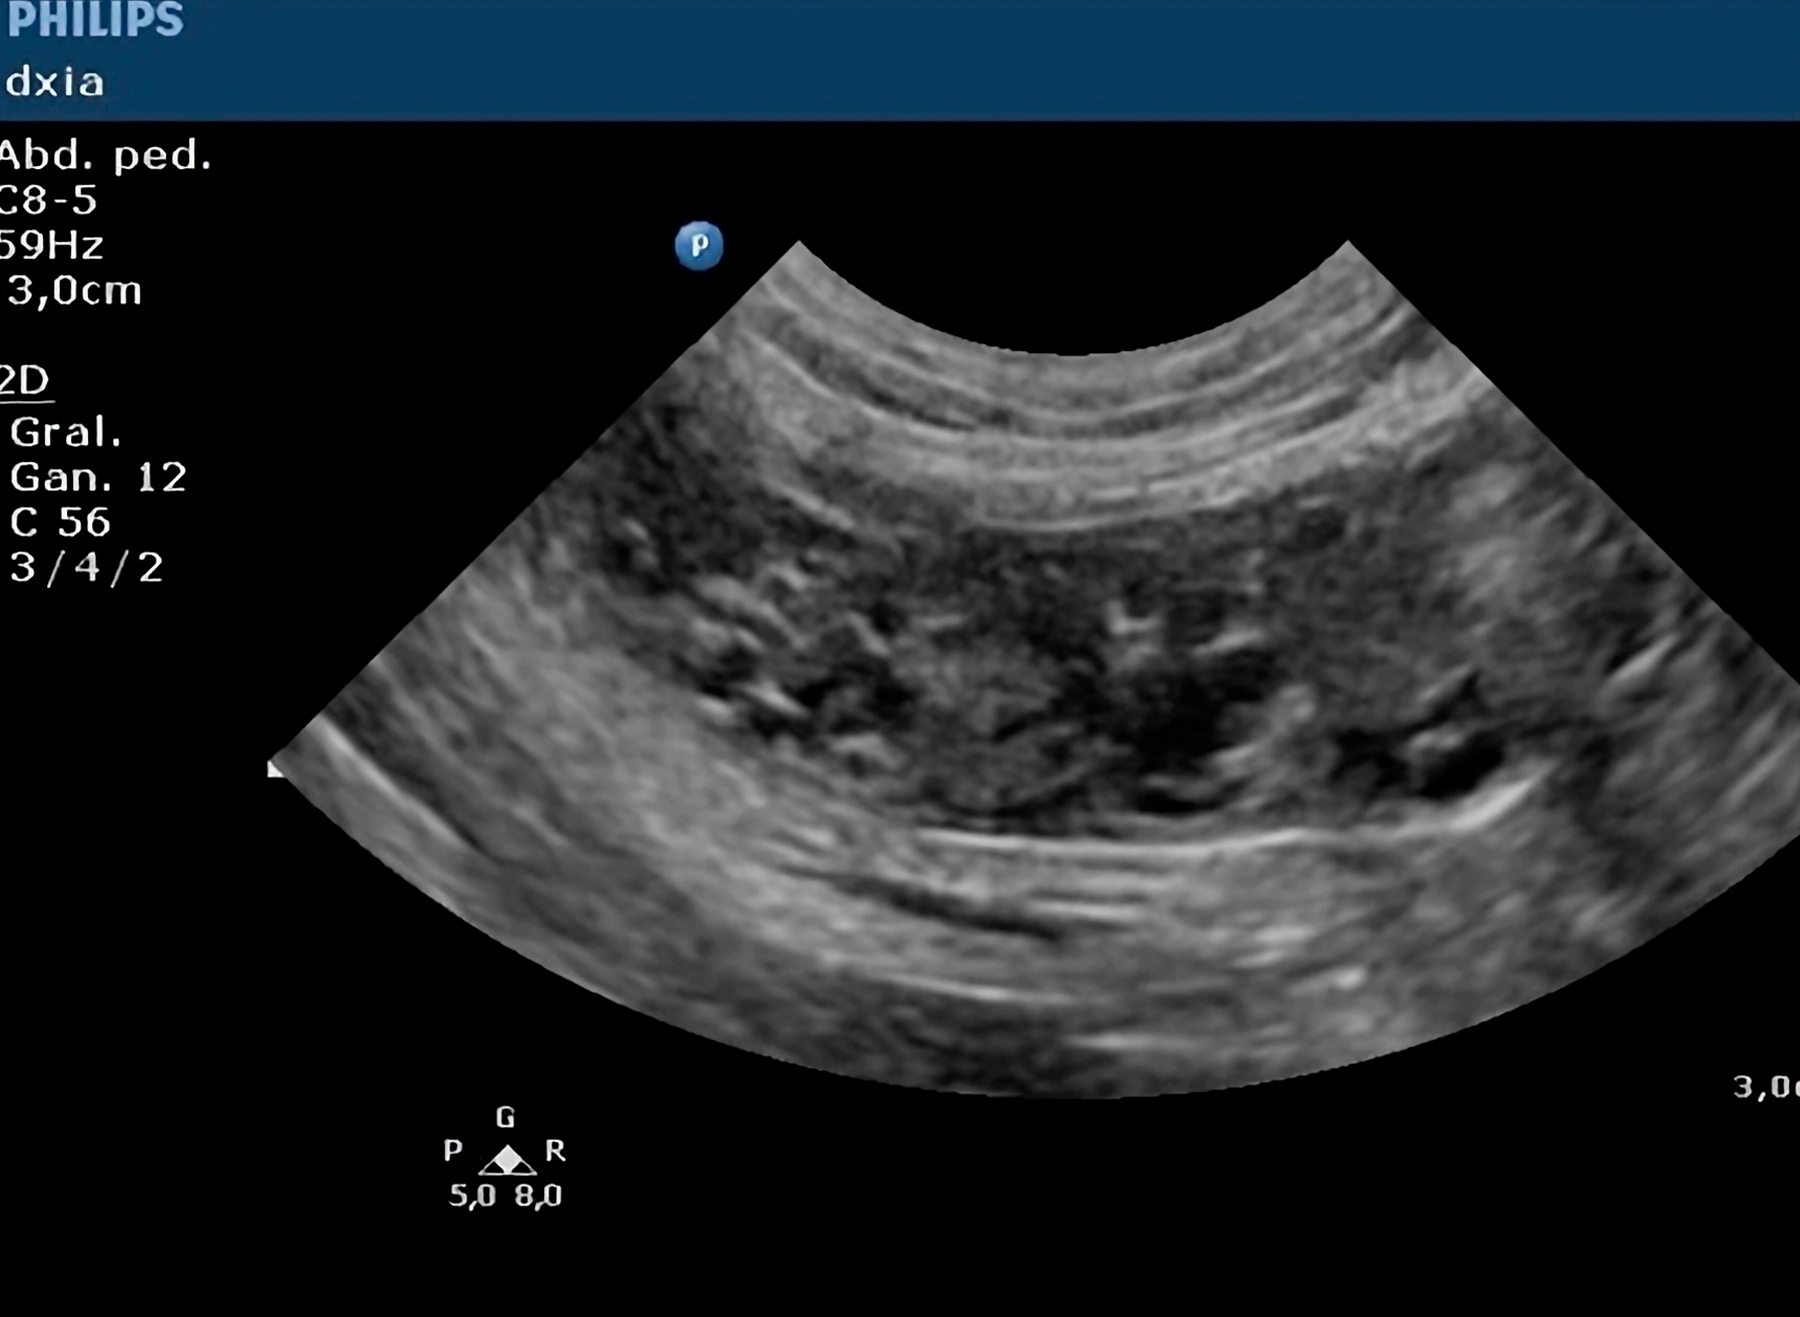

Endometritis Quística

Caso Clínico: Correlación Diagnóstica (Ecografía y Quirúrgica)

Estudio Ecográfico Especializado:

Se identificaron hallazgos ecográficos compatibles con endometritis quística.

Confirmación quirúrgica de la patología. La paciente presentó una evolución postoperatoria óptima con resolución completa del cuadro clínico.